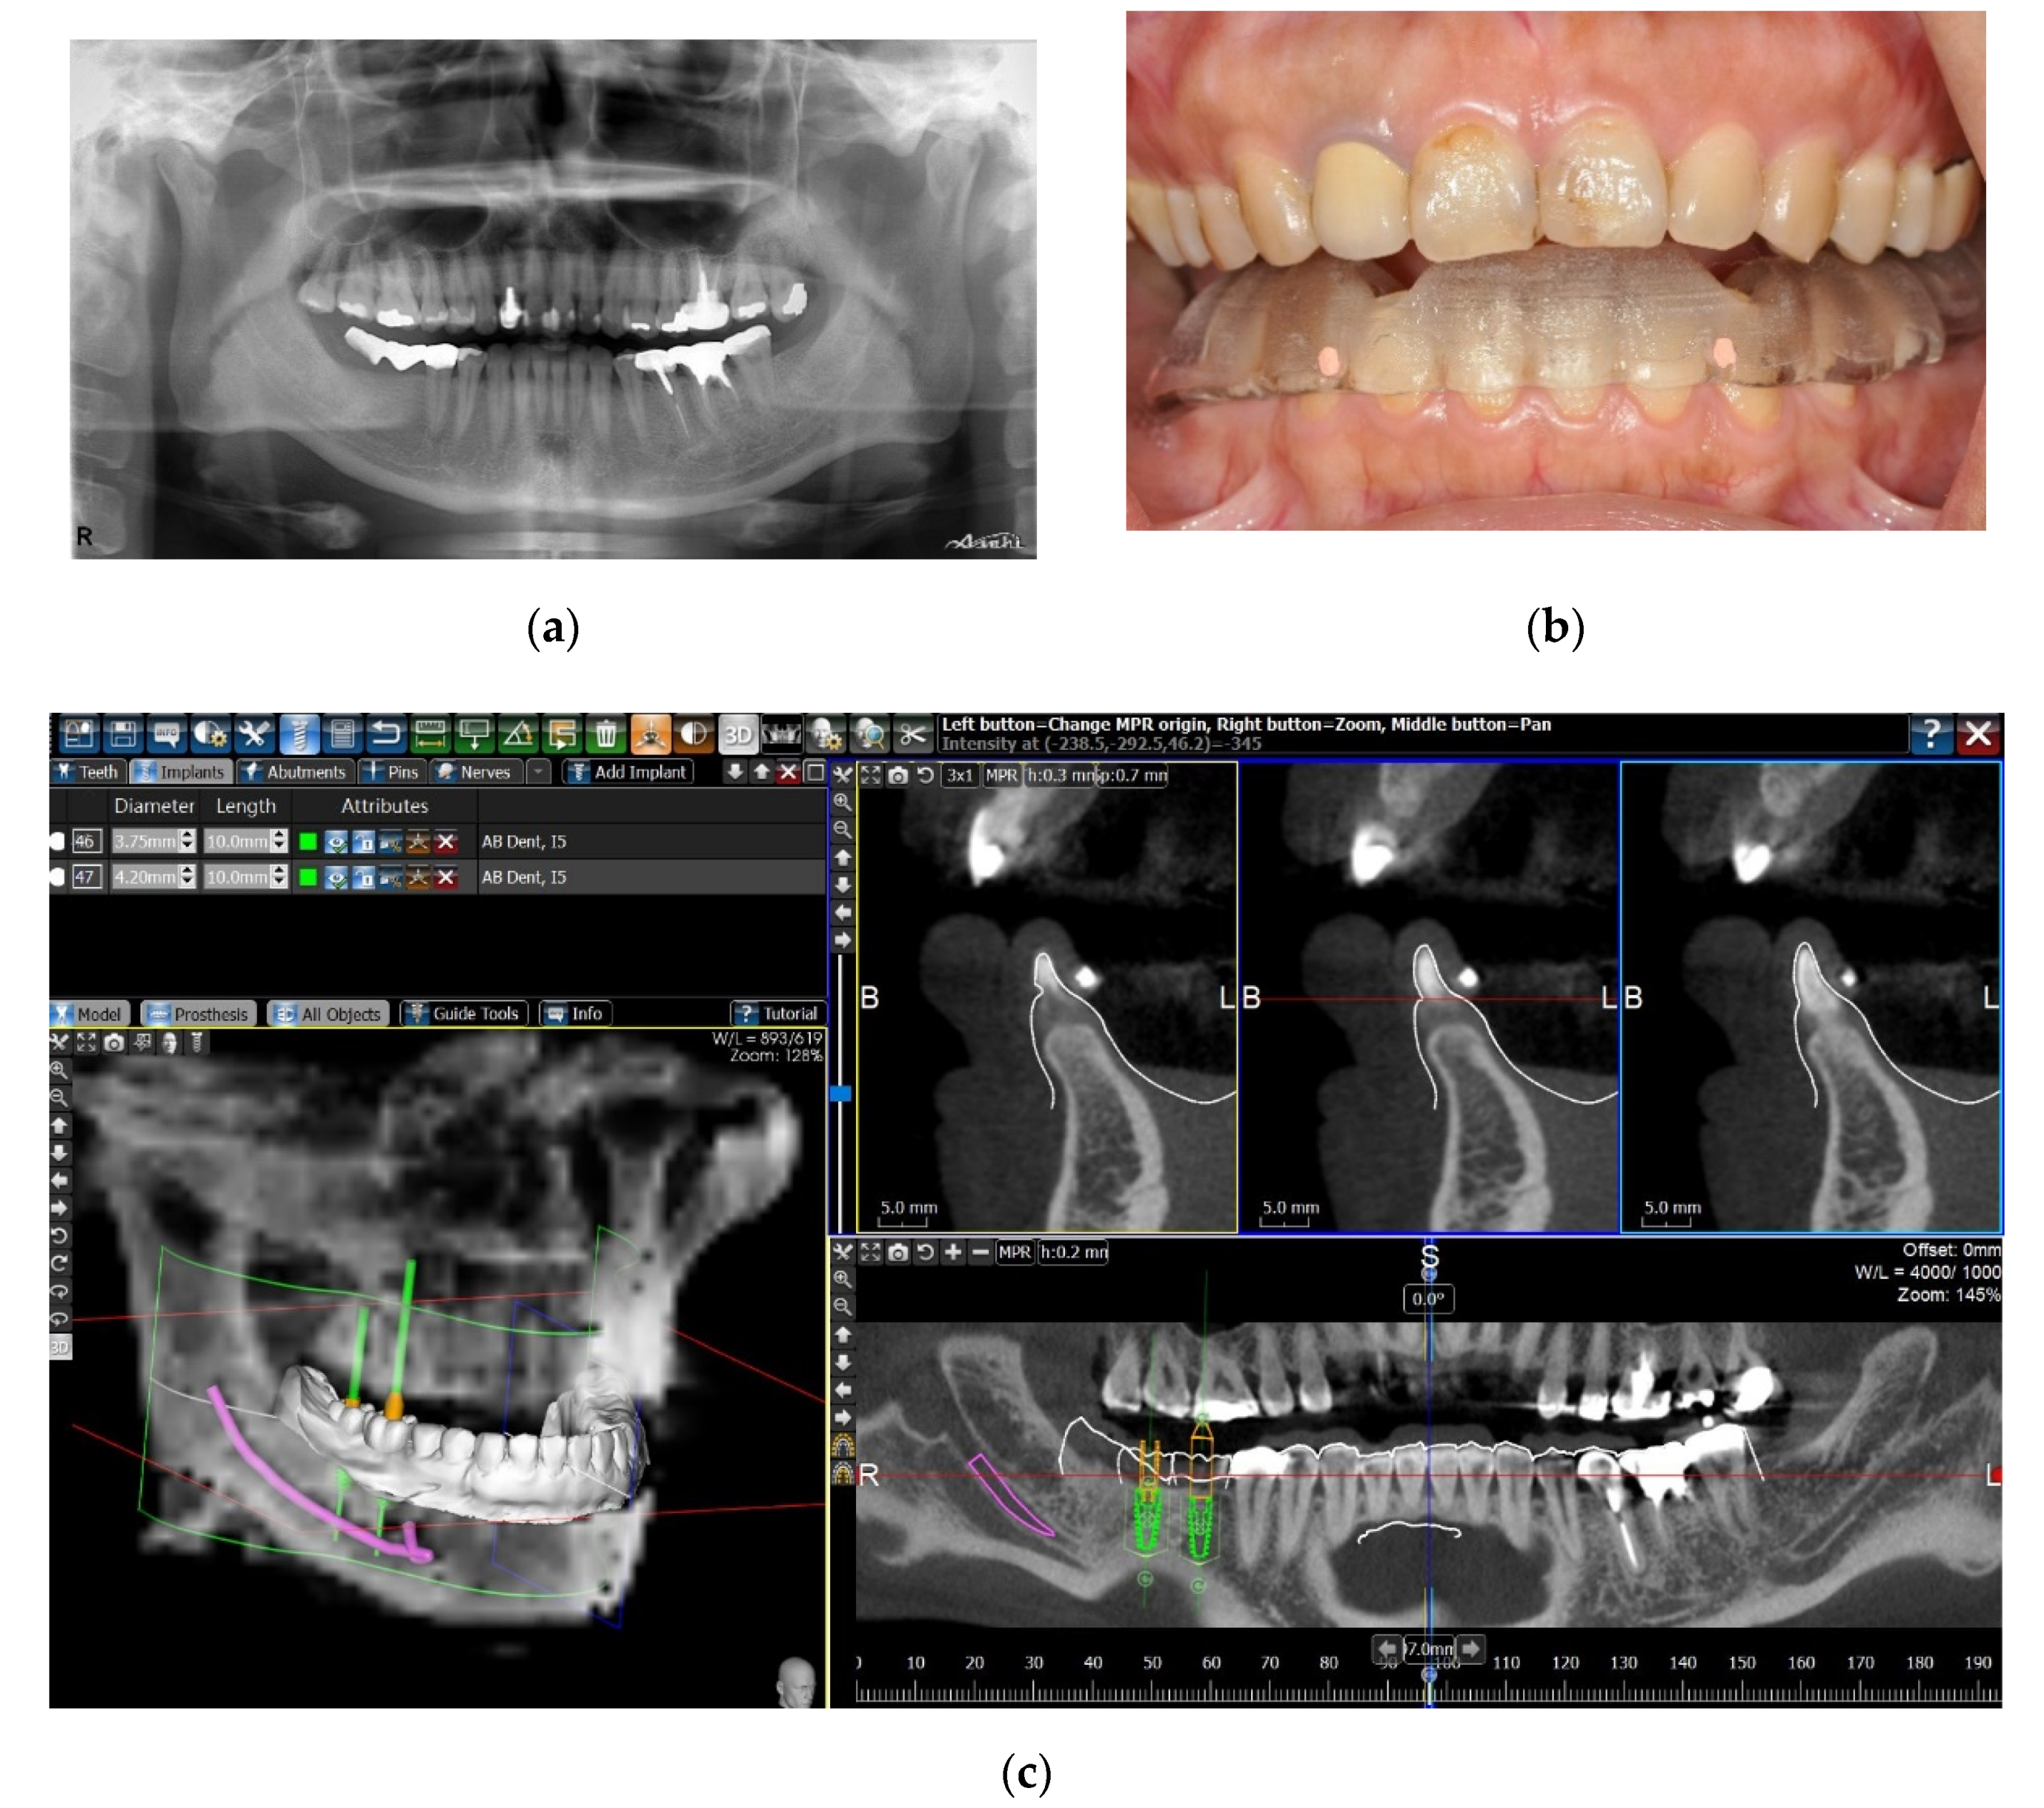

In some cases, insufficient registration points could be set on the dental surface of the digital cast; for example, the number of remaining teeth was not sufficient, the remaining teeth were not satisfactorily distributed for a precise registration, the patients were edentulous, or the streaking artifacts of radiopaque restorations on the CBCT scan hindered the correct registration process. To overcome this challenge, a second method of image registration was chosen. A radiographic template was first designed and fabricated by the SLA process based on the digital dental cast. Radiopaque fiducial markers were set on the template, and the patient underwent a CBCT scan with the SLA radiographic template in the mouth. The image of the fiducial markers could then be identified on both the digital dental cast and the CBCT scan, and the two digital images could be superimposed with the same registration tool of the software, using the fiducial markers as the registration points (Figure 2).

Figure 2. Matching the digital dental cast and the CBCT scan by registration of fiducial markers. (a) A patient with missing right mandibular first and second molars. Because of the streaking artifacts from the radiopaque crowns of bilateral posterior area on the CBCT scan, a direct superimposition with the digital dental cast was challenging. (b) On the basis of the digital dental cast, an SLA radiographic template with gutta percha fiducial markers was fabricated. The patient took a CBCT scan with the radiographic template in the mouth. (c) The image of the fiducial markers could be identified on both the digital dental cast and the CBCT scan, and the two digital images could be superimposed by matching the fiducial markers.